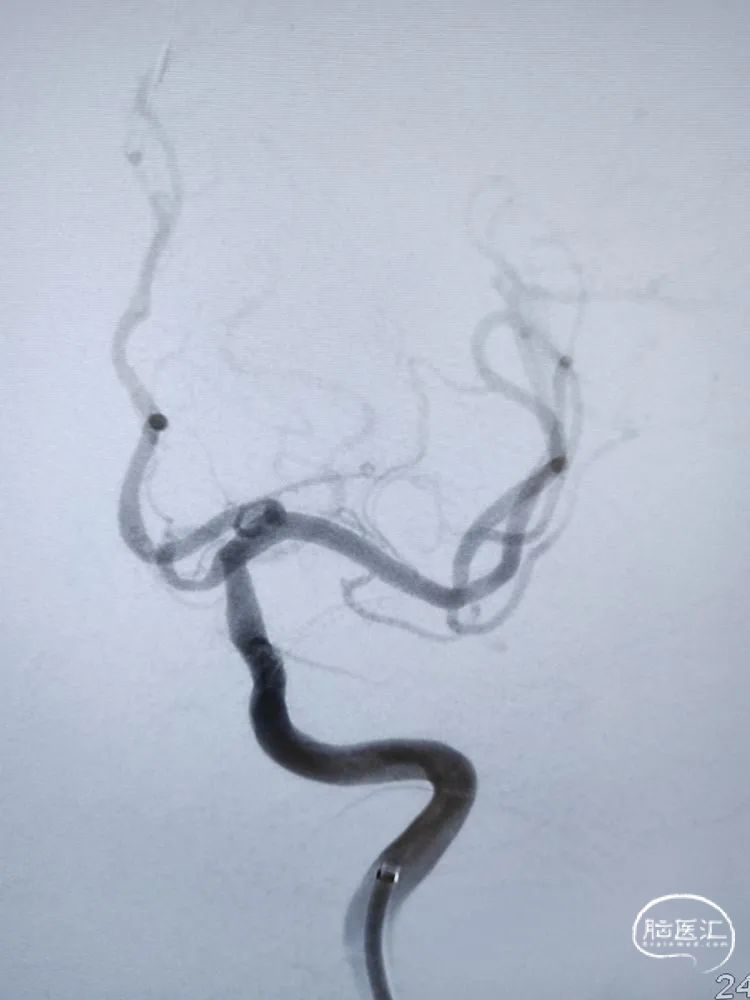

DSA检查:全脑血管造影检查提示左侧颈内动脉海绵窦段-水平段中段重度狭窄。

DSA检查:远端正常段管径约3.22mm,近端接近正常段管径约4.01mm,预估支架长度约12.67mm;合并后交通动脉圆锥。

麻醉成功后,患者平卧位,双侧腹股沟区常规消毒、铺巾,取右侧腹股沟韧带中点下2cm处股动脉为穿刺点,采用Seldinger法穿刺成功,利用置换导丝置入8F鞘。选择侧位工作角度,在8F导引导管支撑下,将6F 115cm颅内支撑导管输送至海绵窦段接近狭窄近端建立稳定通路,大单弯塑形的0.014inch 200cm微导丝顺利通过狭窄段,换成正位工作角度将微导丝安全置于大脑中动脉M2段粗大分支平直段。

支架到位及释放:

在颅内支撑导管的支持下,沿微导丝将4.0mm*13mm Bridge椎动脉雷帕霉素靶向洗脱支架送至狭窄部位,支架到位比较顺利,通过狭窄处支架略有卡顿、微导丝有些回退,支架近端定位在接近正常段管径4mm处,略高于额定压扩张球囊释放支架,球囊缓慢泄张后造影提示支架内血流通畅,支架完全张开贴壁,局部无残留狭窄。